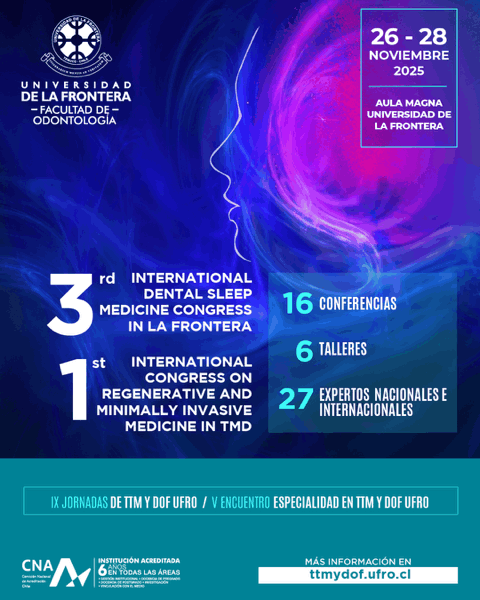

- 16 Conferencias

- 06 Talleres

- 27 Expertos nacionales e internacionales.

Aula Magna Universidad de La Frontera.

26 al 28 de Noviembre de 2025